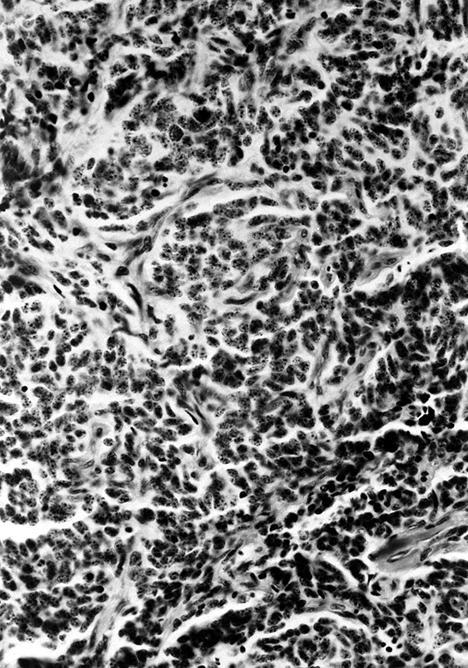

Microscopic (histologic) description

- Wide variety of morphology, can mimic any other thyroid malignancy

- Round, plasmacytoid, polygonal or spindle cells in nests, cords or follicles; often mixtures of these cells

- Round nuclei with finely stippled to coarsely clumped chromatin and indistinct nucleoli, occasional nuclear pseudoinclusion

- Eosinophilic to amphophilic granular cytoplasm due to secretory granules

- Generally low mitotic figures

- Stroma has amyloid deposits from calcitonin, prominent vascularity with glomeruloid configuration or long cords of vessels (Am J Surg Pathol 1995;19:642), coarse calcifications, occasional psammoma-like bodies

- Occasionally marked neutrophilic infiltrate, oncocytic tumor cells, papillary patterns

Variants (important for differential diagnosis, most are of no prognostic importance):

- Paragangioma-like variant:

- Nested tumor cells, mimics paraganglioma (Mod Pathol 1990;3:581)

- Nest-like pattern with pigmented dendritic cells resembling sustentacular cells (Arch Pathol Lab Med 1994;118:1041)

Microscopic (histologic) images

Contributed by Shuanzeng Wei, M.D., Ph.D., Joseph Christopher Castillo, M.D. and Mark R. Wick, M.D.

AFIP images